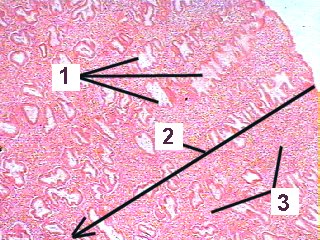

This is a higher magnificaiton of a section through the endometrium during the secretory phase.

Fig 88-003 1. Coiled glands with large lumens

2. Zona functionalis

3. Stroma of loose connective tissue with a large amount of amorphous ground substance, cells and reticular fibers